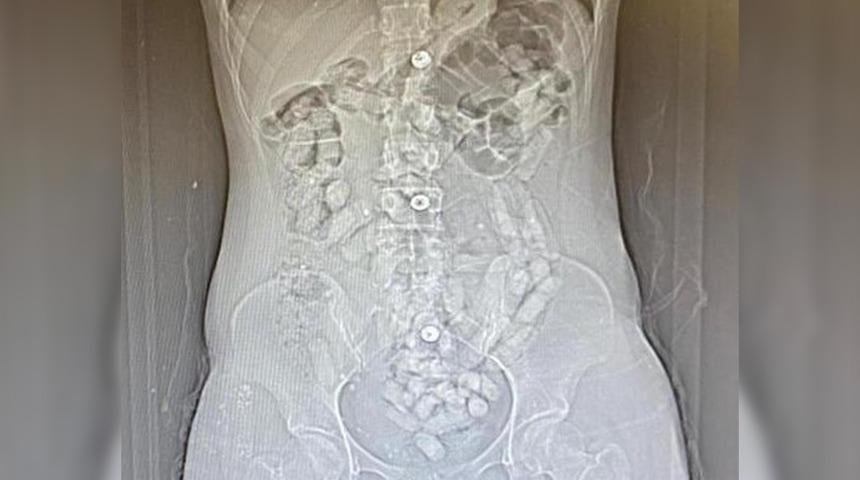

Savcılıktan alınan kararla götürüldükleri hastanede yapılan tomografi çekiminde, Khadıjeh S.'nin mide ve bağırsak bölümünde 31 parça halinde yaklaşık ağırlığı 252,52 gram ile Samıra T.'nin de 64 parça halinde 440,78 gram olmak üzere toplam 95 parça halinde 693,3 gram Afyon sakızı ele geçirildi. Gözaltına alınan şüpheliler, emniyetteki sorgularının ardından 'Uyuşturucu madde ticareti yapmak' suçundan adliyeye sevk edildi. Allahnıaz S. adli kontrol şartıyla serbest kalırken; Khadıjeh S., Samıra T. ve Raheleh Y. tutuklandı.